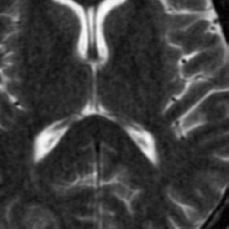

(b) FLAIT brain

Figure 2: Test Images.

We turn now to test TDIHT for high dimensional signals. We test the performance of several MRI images: the Shepp-Logan phantom, FLAIT brain image, T2 Sagittal view of the lumbar spine and the circle of Willis. The first image is of size 256×256256256256\times 256, while the other are of size 512×512512512512\times 512. They are all presented in Fig. 2.

We focus on the recovery of these images from a few number of Fourier measurements. With 𝛀𝛀{\mathbf{\Omega}} set to be the undecimated Haar transform with one level of resolution (redundancy four) and 𝐃𝐃\mathbf{D} its inverse transform, we succeed to recover the phantom image using only 181818 sampled radial lines, which is only 6.5%percent6.56.5\% of the measurements. This number is only slightly larger than the number needed for GAP, relaxed ASP (RASP) and Relaxed ACoSaMP (RACoSaMP) in [10, 38]. The advantage of TDIHT over these methods is its low complexity as it requires applying only 𝐌𝐌{\mathbf{M}} and its conjugate and 𝛀𝛀{\mathbf{\Omega}} and its inverse transform while in the other algorithms a high dimensional least squares minimization problem should be solved. Note also that for AIHT and RAHTP the number of radial lines needed for recovery is 353535 and for IHT (with the decimated Haar operator with one level of resolution) we need more than 505050 radial lines.